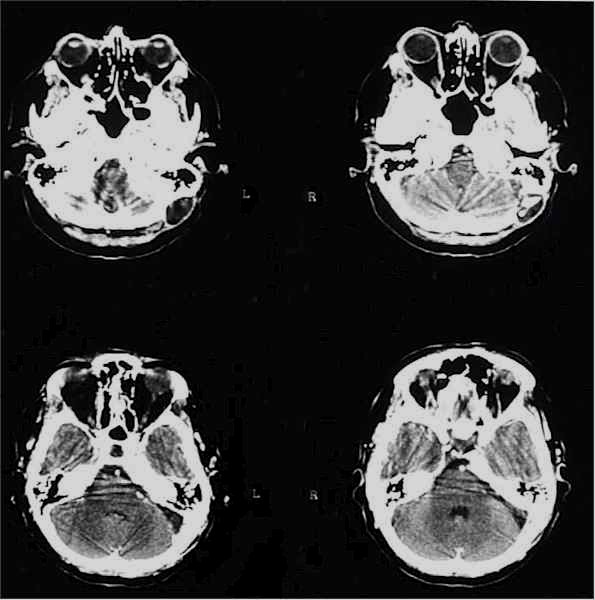

TC preoperatoria

TC postoperatoria

RM preoperatoria

RM postoperatoria